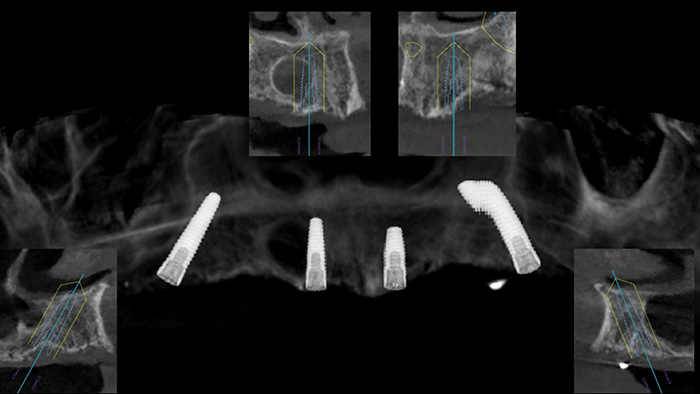

Fig. 2 : Indication de la pose de 4 implants maxillaires selon les zones de E. Bedrossian (Bedrossian E et al. Fixed-prosthetic Implant Restoration of the Edentulous Maxilla: A Systematic Pretreatment Evaluation Method. J Oral Maxillofac Surg 2008;66:112-22 ) et suivant le protocole de P. Malo (All-on-4 immediate-function concept with Brånemark System implants for completely edentulous maxillae: a 1-year retrospective clinical study.

Maló P, Rangert B, Nobre M.).